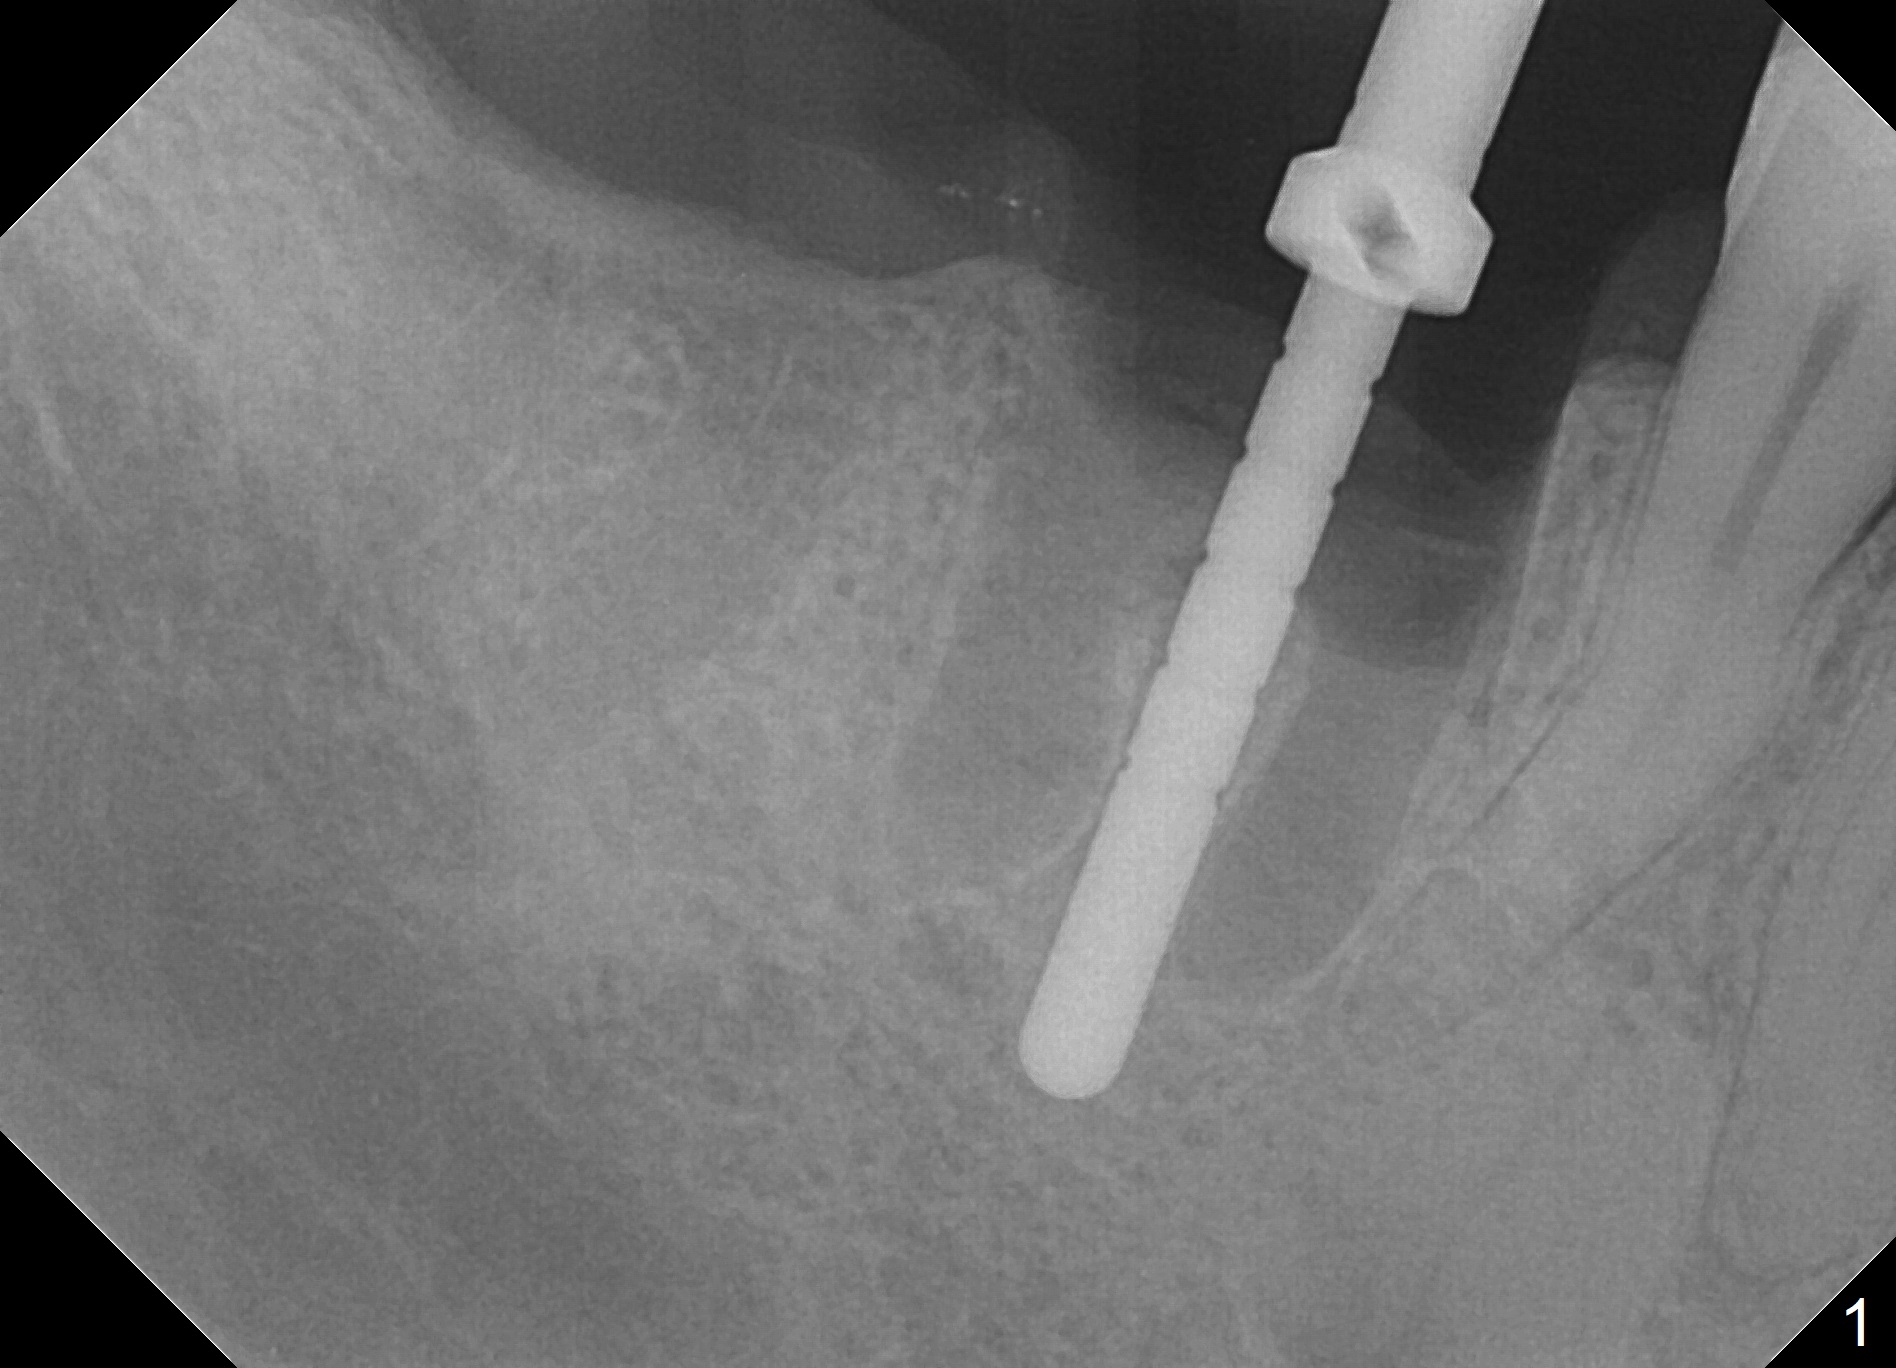

Extraction is difficult due to hard bone and brittle, curved roots of the tooth #30; initial depth in the septum is 14 mm (gingival level, Fig.1). Then the depth increases to 17 mm; with sequential osteotomy using 2.8 mm to 4.8 mm Magic Drills (MD), a 5x9 mm dummy implant is placed incompletely due to hard bone (Fig.2). After use of 5.3 mm MD for ~ 15 mm, the dummy implant is placed to the depth (Fig.3). The definitive IBS implant (5x13 mm) is placed with 50 Ncm; a 6.5x5.7(4) mm abutment is placed with allograft filling the gap (* and arrow).